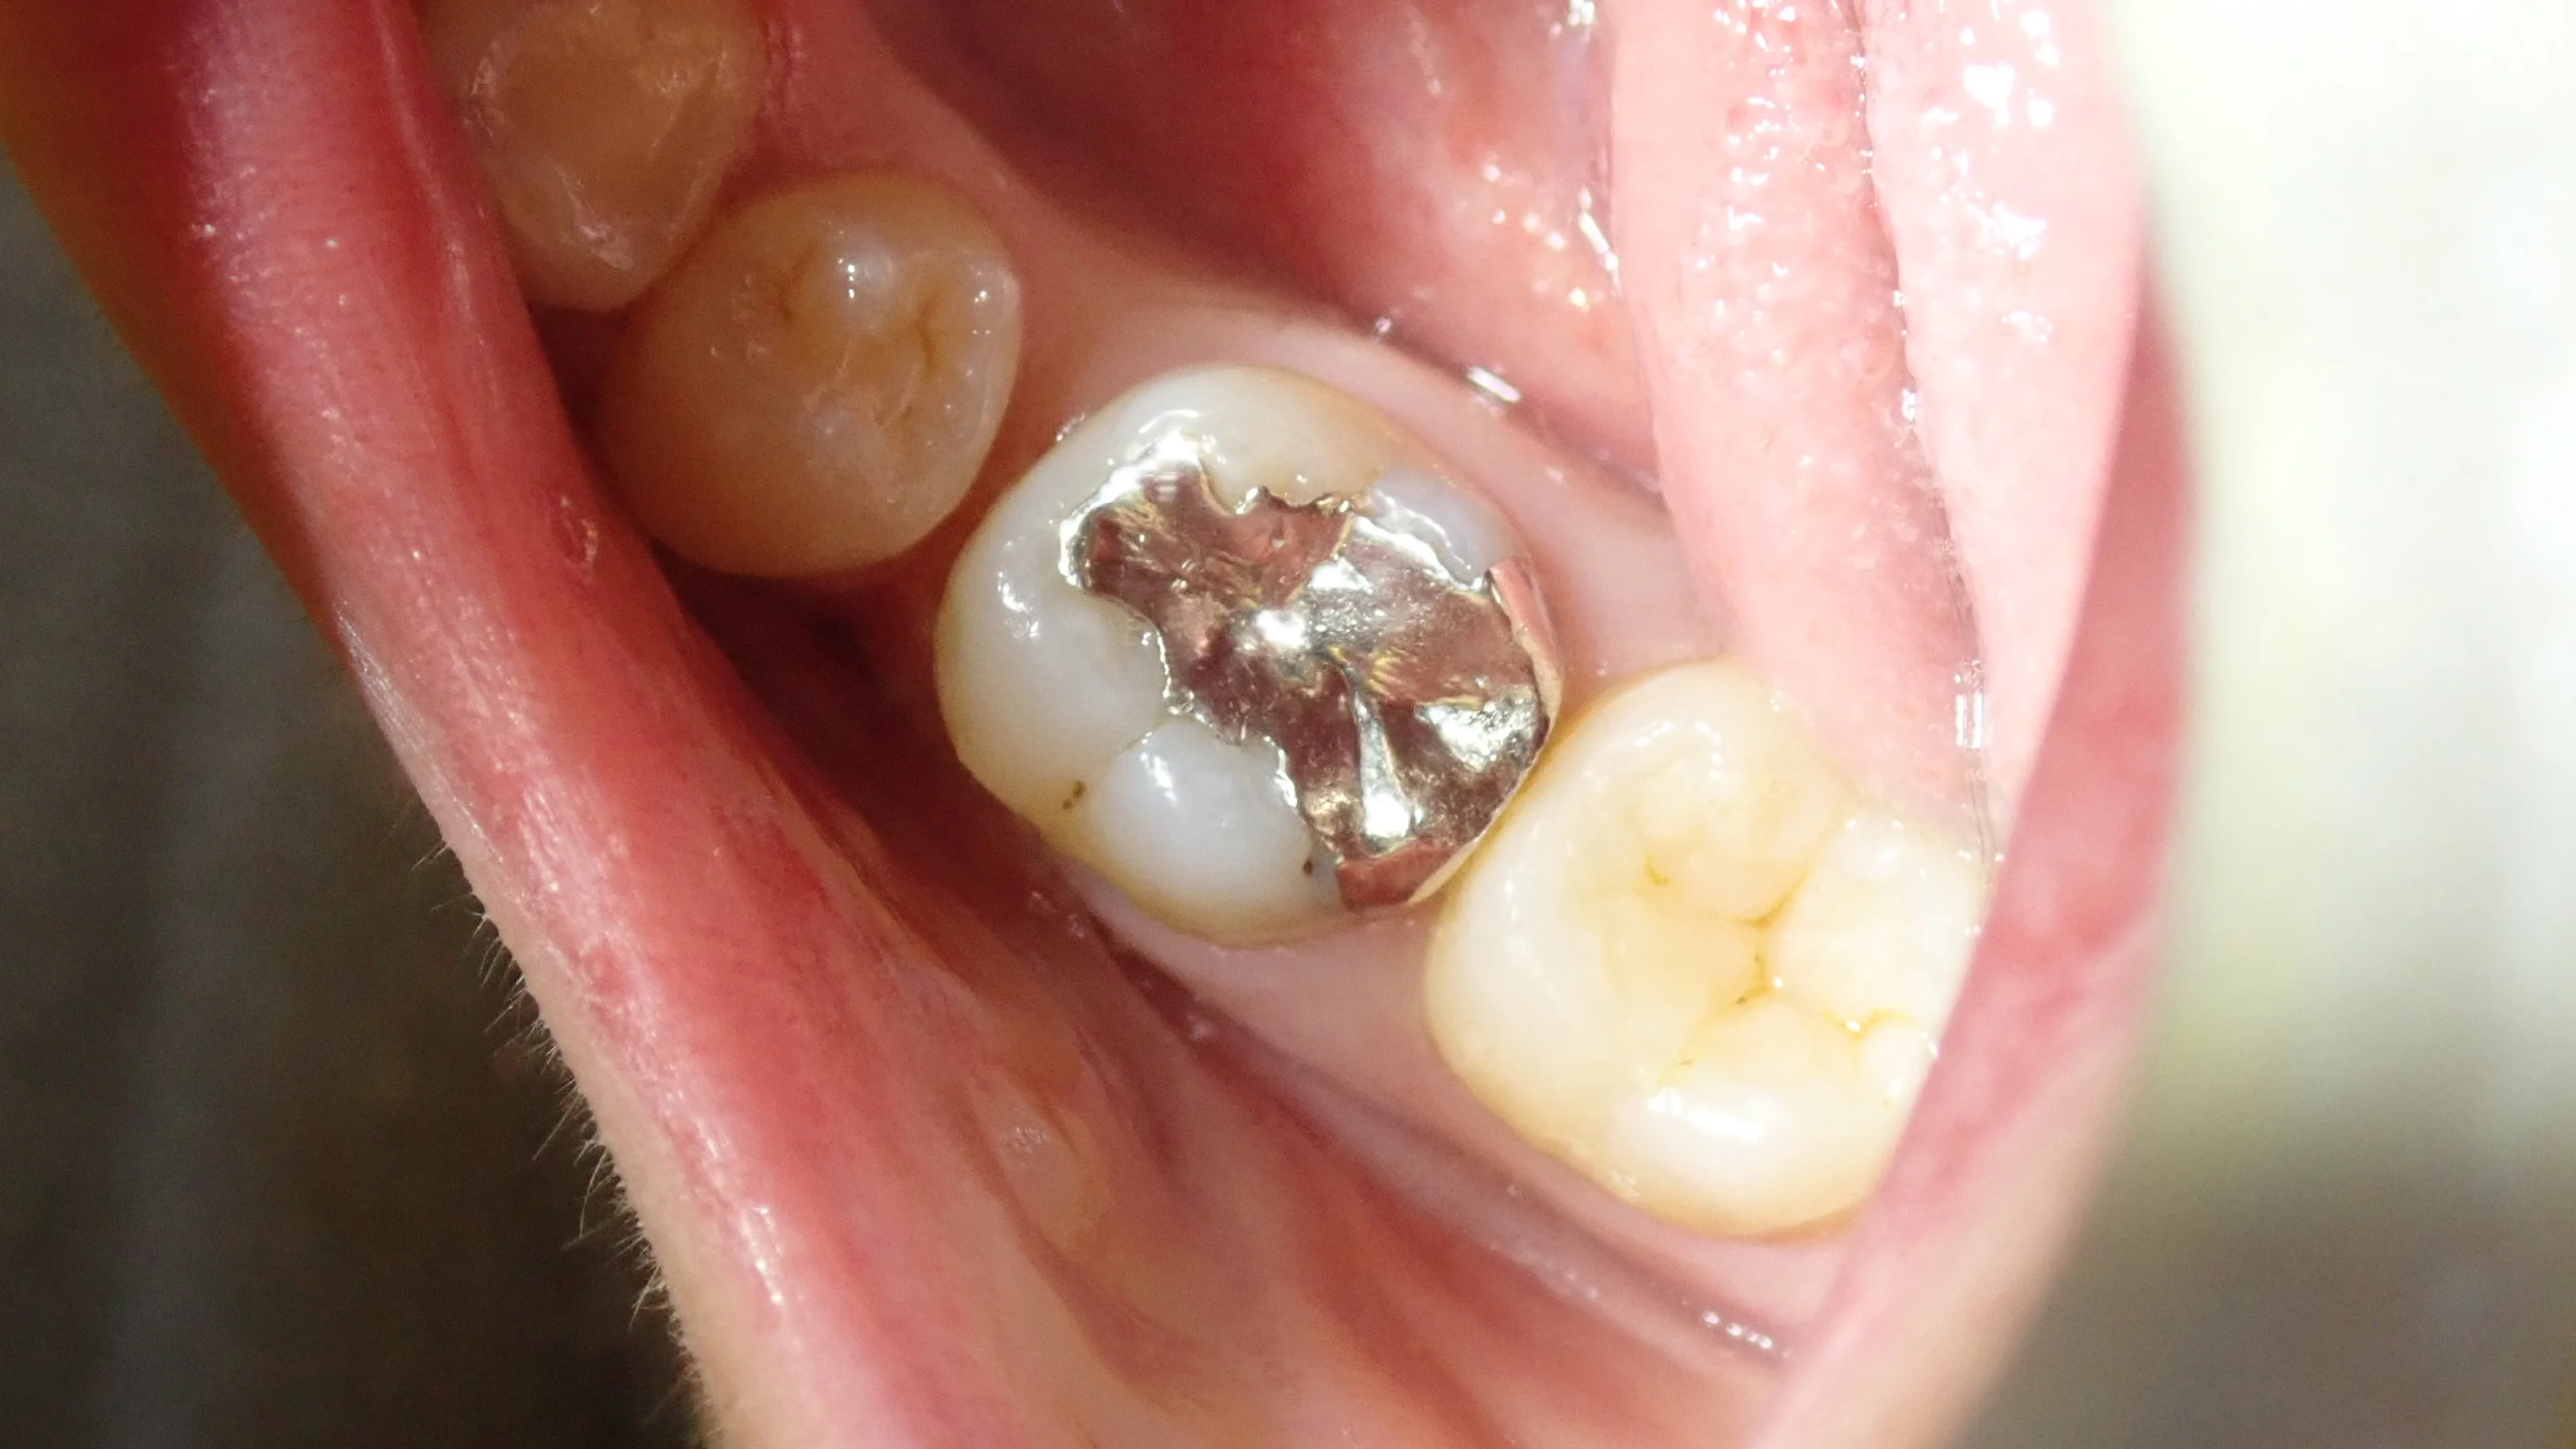

金属を軽くとったのがこちらですね。

で、完全に虫歯を取り切ったらこうなりました。

後ろの歯との間が非常に深くなっています。

手前の歯との間についても、虫歯だったため、歯が少なくなってしまいました。